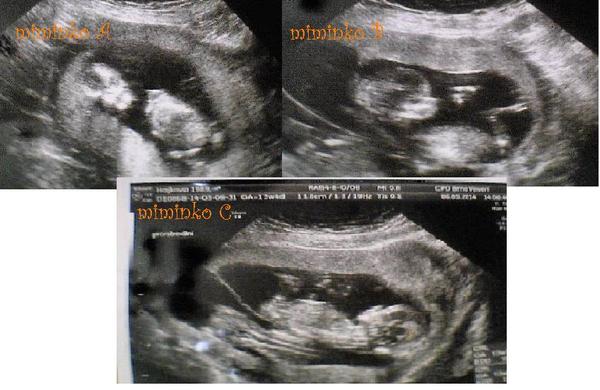

@hankamisa Ahoj tak mimiska se mají dobře, podle pana dr.Vlašína z Prenatalu mají velkou šanci vydržet co nejdýl v bříšku.Segra je vysoká tak mají dost místa.Jinak předpokládaný termín císaře je prozatím 10.10.2014.Segra se cití dobře akorát má sníženou funkci štítné žláži tak papá Letrox.A 20.6. se bude vdávat. 🙂

Jsou krásní! Co to bude ještě neví? Jinak hodně štěstí a zdravá miminka 🙂